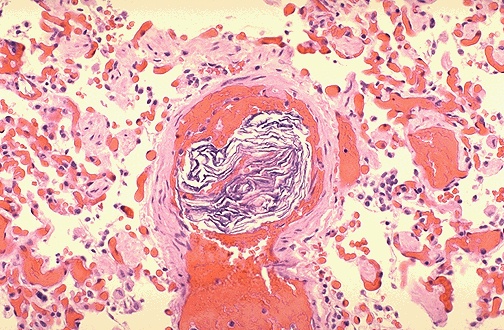

Saddle embolus of pulmonary artery without acute cor pulmonale i26.99 other pulmonary embolism without acute cor pulmonale i27.0 primary pulmonary hypertension i27.1 kyphoscoliotic heart disease i27.20 pulmonary hypertension, unspecified i27.21. Pulmonary Pathology

Pulmonary Pathology from library.med.utah.edu